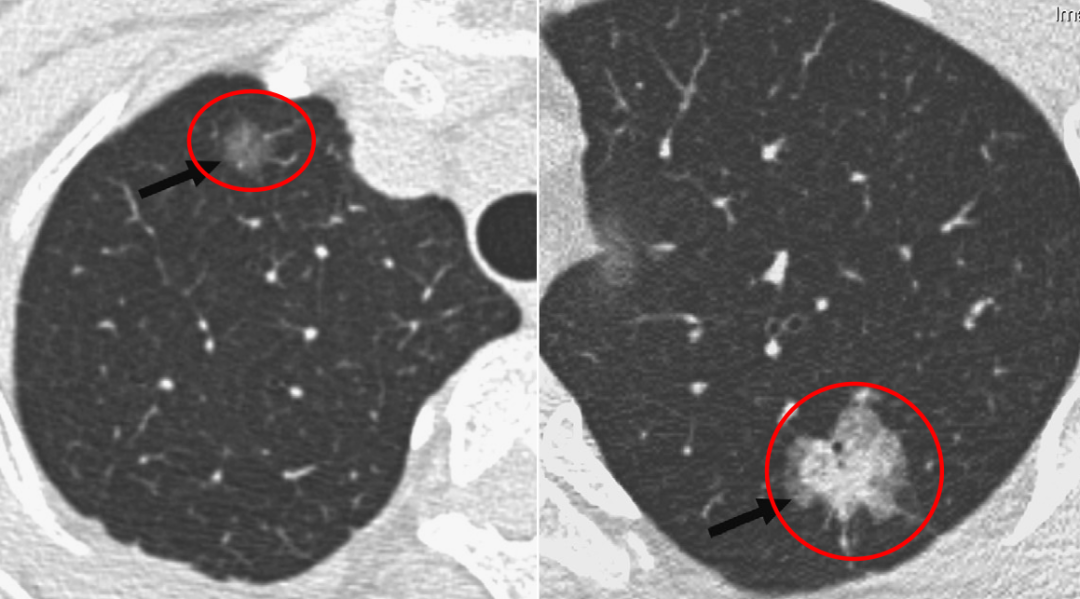

左图:纯磨玻璃结节

右图:部分实性的磨玻璃结节

其实大家比较担心的是部分实性的磨玻璃结节,右图的结节看起来就比左图「实」很多,大家一眼就能看到这个病灶。这个结节的实性成分很多,里面还有空泡、分叶和胸膜的牵拉。对于这个结节来说,有经验的医生一看可能就会觉得恶性程度比较大,所以对于这样的结节,医生会建议去做手术切除。因此,磨玻璃结节的表现的性质非常重要,不能从报告上完全读出来它究竟是恶性还是良性,还需要有经验的医生根据CT影像学的表现仔细辨别。